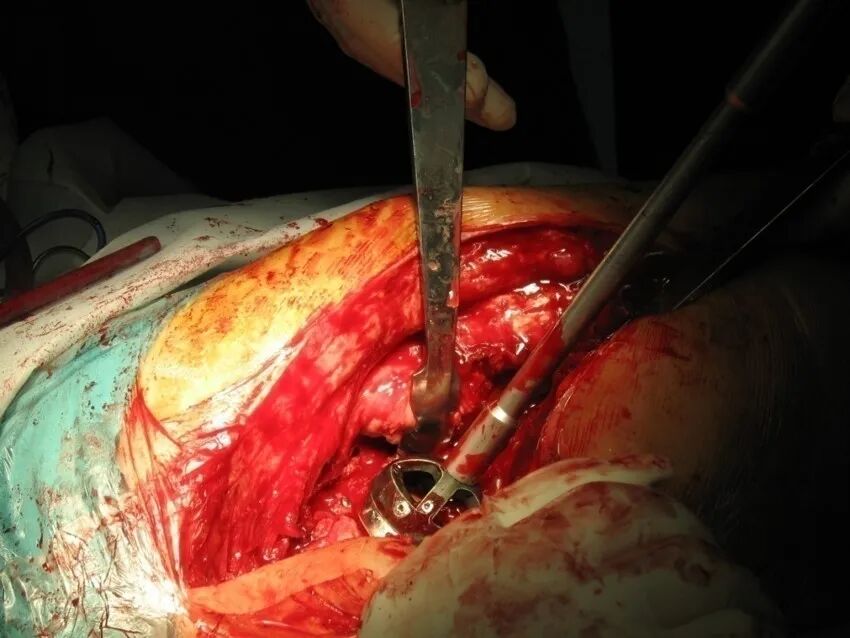

切开复位